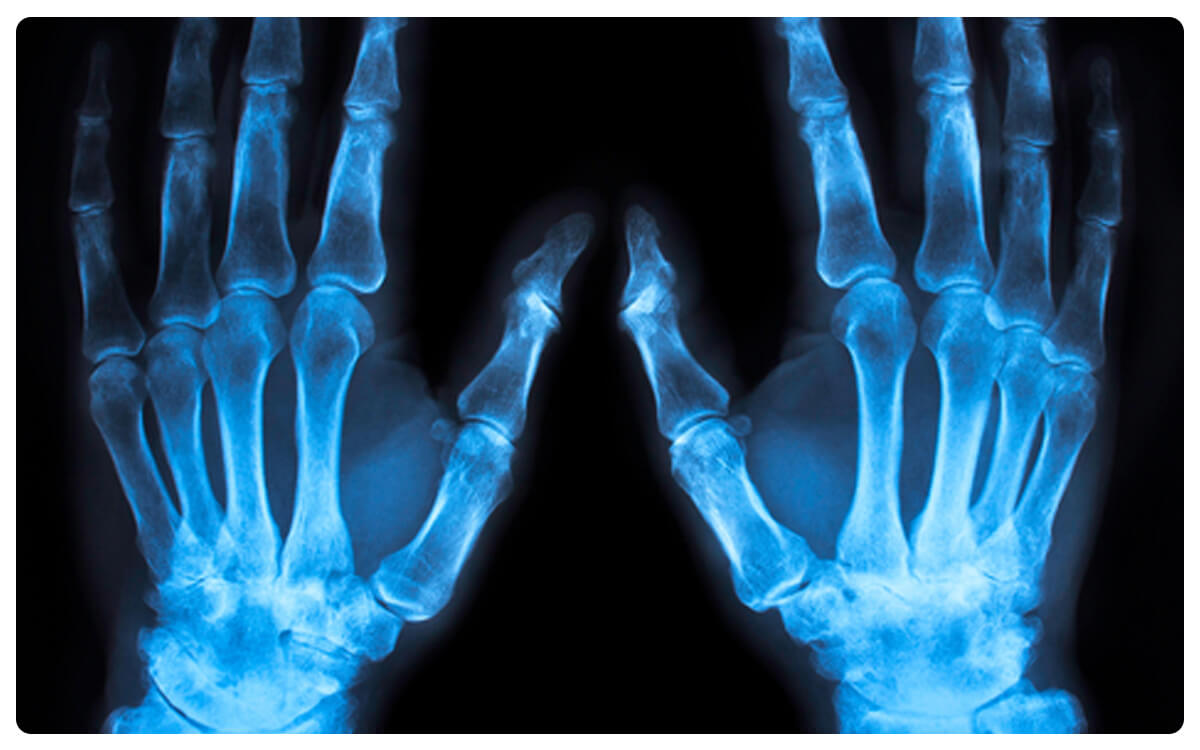

La Radiografía de Mano en Proyección Anteroposterior (AP) se presenta como una herramienta esencial en la radiología diagnóstica, ofreciendo una visión detallada y estructurada de la anatomía y posibles afecciones de la mano. A través de la emisión controlada de radiación, esta técnica no invasiva proporciona imágenes bidimensionales que permiten la evaluación de los huesos, articulaciones y tejidos circundantes en la región de la mano desde una perspectiva frontal.

La Radiografía de Mano en Proyección AP desempeña un papel fundamental en la detección y diagnóstico de fracturas, desplazamientos, anomalías óseas y otras patologías que afectan la mano, brindando información esencial para la toma de decisiones clínicas informadas y el manejo adecuado de las afecciones de la mano.